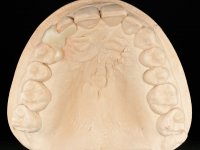

To define the dental zone to be covered by the Maryland bridge retainers, the patient was asked to perform maximum intercuspidation movements, and the contact points were marked with articular paper. Tooth preparation of the interproximal surfaces was made, to create a prosthetic insertion axis. It was sought that the mesio-distal diameter at the incisal level was equal to the diameter mesio-distal at the cervical level, that is to say, the interproximal walls were parallelized. Tooth preparation was done with fine grain diamond drills, and later polishing was done with abrasive discs. Color information was collected even before confection of the impression, to avoid dehydration of the arcade. Definitive impression was made using wash technique impression with silicone of heavy and regular consistency, both with fast setting, and a working plaster model was prepared in the lab. A laboratory scanner was used to scan the working model, and later, the infrastructure for the Maryland bridge was made using a CAD-CAM process. Ceramic was placed on this subframe. A ceramic adhesive was applied to the internal surface of the wings and connectors, which would enable bonding to the adjacent teeth. The adhesive bridge was bonded in the mouth following the conventional bonding technique. After bonding, the protrusion and laterality movements were carefully checked to avoid undesirable contacts.